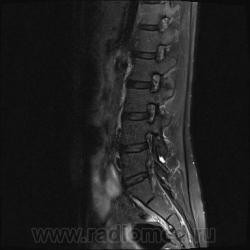

Пациентка 25 лет обратилась к неврологу с жалобами на слабость, изменение походки. Раньше не обследовалась.

Я специально сделал изображения потемнее, чтобы выделить патологию (жировую дегенерацию) именно мышечной ткани.

Гм, как это я пропустил эту публикацию. Поясничные мышцы замещены жировой тканью; т.е. Они выглядят "белыми" на Т1 и Т2, в последовательности с подавлением жира, соответственно сигнал уходит; и они "тёмные". Такую картину я видел у пожилых, иногда у пациентов после операции на позвоночнике. По поводу болезни Штейнерта, должна быть клиника, изменения и гипотония/атония мышц других локализаций. На основании только МРТ ПОП не совсем убедительно. Вот небольшая ознакомительная статейка.